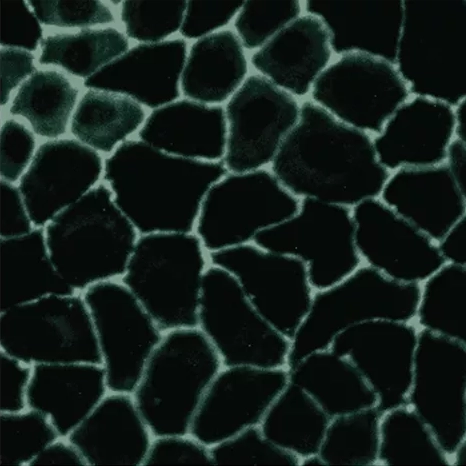

While ION* works in several ways to counteract the effects of gluten at the gut lining, gluten is where this innovative humic extract blend really shines. The molecules that make up ION* help to activate the enzyme, DPP4, which works to remove the toxic peptides found in gluten. By sparking this initial enzyme production, ION* can maintain low levels of zonulin and combat tight junction damage. And by maintaining tight junction integrity, even in the face of glyphosate toxicity, ION* is further helping to defend against unnecessary immune response associated with gluten exposure.

By reducing free radical damage and upregulating enzymes that help degrade gliadin peptides, ION* Gut Support helps to protect the gut lining against damage from gluten, further defending your immune system from the onslaught of inflammatory foods and toxins.